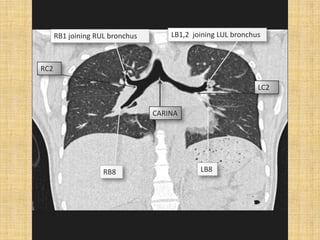

RB1 joining RUL bronchus       LB1,2 joining LUL bronchus

RC2

LC2

CARINA

RB8                      LB8